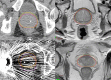

Methods: A common set of computed tomography (CT) and magnetic resonance imaging (MRI) data sets were used to assess prostate contouring consistency before, immediately after and 12 months following an EI. No further EIs were provided after the initial EI. Contour variation was assessed using the volume ratio (VR), defined as the ratio of the encompassing volume to common volume.

Results: Of the original five radiation oncologists (ROs) at baseline, four completed all assessments, and one was unavailable at 12 months follow-up. At 12 months, mean VR deteriorated by 3.2% on CT and 1.9% on MRI compared to immediately post EI. Overall, compared to the pre-EI baseline VR, an improvement of 11.4% and 10.8% was demonstrated on CT and MRI, respectively.